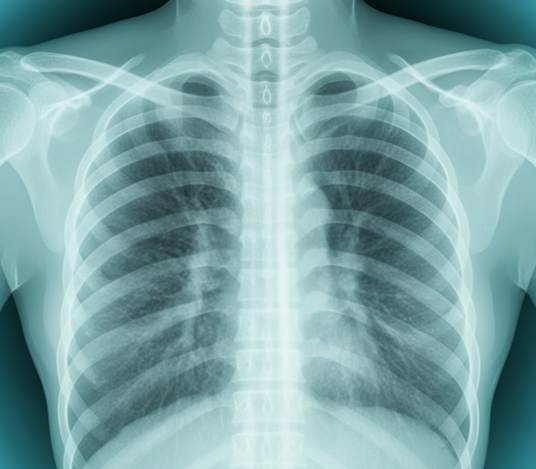

Urgent care also plays a crucial role in preventing complications from upper respiratory infections. While many URIs resolve on their own, untreated infections can sometimes lead to secondary issues such as bronchitis, ear infections, or pneumonia. By seeking timely care at NovaHealth Urgent Care, patients can receive guidance on symptom management, medication usage, and follow-up care if needed, reducing the likelihood of complications.